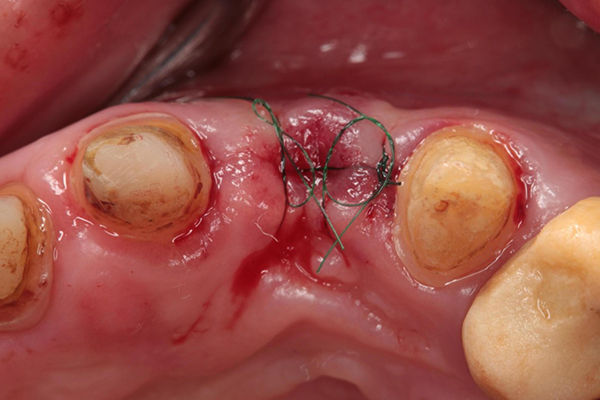

左上2に関しては、歯肉のボリュームが不足しているために、旧来の被せ物(ブリッジ)では、歯の長さが長く、歯肉との隙間が大きいために物が詰まりやすい状態でした。そこで歯肉のボリュームが不足している部分に、上顎口蓋から歯肉組織を一部採取し、移植することとしました。組織移植後はブリッジのダミーの歯が、あたかも歯肉から歯が生えているような自然さを出すために、仮歯の形を修正し、歯肉の形態を整えていきました。

左上2部への組織移植術直後